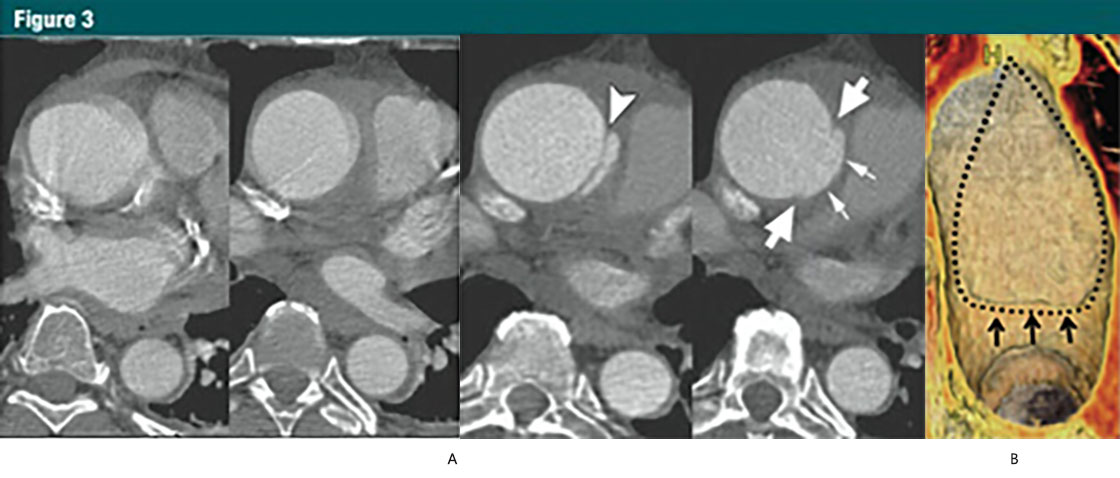

圖3 升主動(dòng)脈局限性內(nèi)膜撕裂

(A)上方:無心電門控的CTA顯示升主動(dòng)脈運(yùn)動(dòng)偽影,模糊;下方:12小時(shí)后,心電門控 CTA示:升主動(dòng)脈近端內(nèi)膜皮瓣(箭頭),伴隨一個(gè)侵蝕邊緣的局限性內(nèi)膜撕裂。局限性內(nèi)膜撕裂的邊緣(大箭頭)和主動(dòng)脈壁破壞形成的突起(小箭頭)清晰可見。這些微妙細(xì)節(jié)如果沒有使用心電門控是不可見的。

(B)VR重建顯示腔內(nèi)一側(cè)6cm長的損傷。一個(gè)小的破損皮瓣(細(xì)箭)代表撕裂的起始端,并一直延伸到主動(dòng)脈弓的近端。虛線,代表撕裂的邊緣。(轉(zhuǎn)載,許可,引用24。)

In a small number of patients with medial disease, a superficial/partial thickness tear develops (the equivalent of a primary intimal tear) without the development ofa separate flow channel or accumulation of intramural blood. These rare lesionsare referred to as limited tears or limited dissection and tend to have subtle imaging findings when compared with classic dissection (30,33,36)(Fig 3).